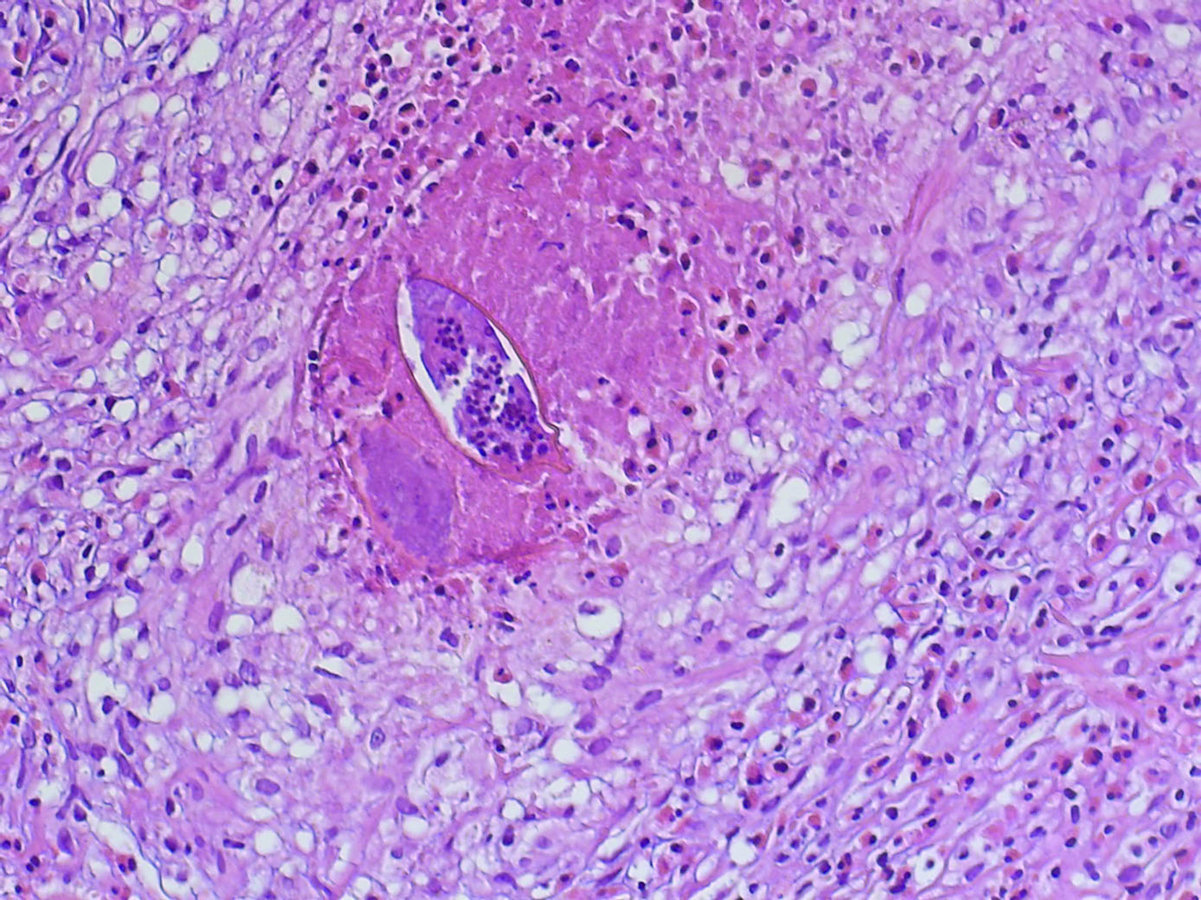

Nachträglich wurde der Wurmfortsatz biopsiert. Neben einer eosinophilen Entzündung fanden sich auch Schistosomeneier. Nachträglich wurde der Wurmfortsatz biopsiert. Neben einer eosinophilen Entzündung fanden sich auch Schistosomeneier. © Mit freundlicher Genehmigung von Dr. Christian Kraef, c.kraef@uke.de, Department of Tropical Medicine, Bernhard Nocht Institute for Tropical Medicine & I. Department of Medicine, University Medical Center Hamburg-Eppendorf, Hamburg

Dr. Christian Kraef von der I. Medizinischen Klinik am UKE und seine Kollegen können im Blut und Ejakulat über PCR den Befall mit Schistosoma haematobium nachweisen. Zusätzlich finden sie vitale Eier des Pärchenegels in der Spermaprobe. Die nachträgliche Histologie des entfernten Appendix identifiziert ebenfalls Granulome mit Wurmeiern. Eine dreitägige Therapie mit Praziquantel (40 mg/kg KG oral) führt zur vollständigen Ge­nesung.

Neben einer eosinophilen Entzündung fanden sich auch Schistosomeneier. Neben einer eosinophilen Entzündung fanden sich auch Schistosomeneier. © Mit freundlicher Genehmigung von Dr. Christian Kraef, c.kraef@uke.de, Department of Tropical Medicine, Bernhard Nocht Institute for Tropical Medicine & I. Department of Medicine, University Medical Center Hamburg-Eppendorf, Hamburg